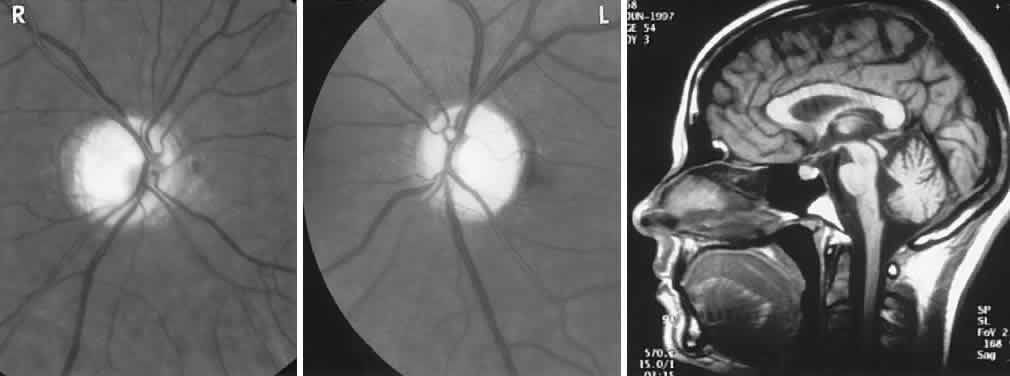

The retinal variety may be admixed in a person who suffers the more conventional attacks of migraine. It is presumed that vasospasm in the retinal circulation determines transient hypoxia, perhaps somewhat similar to the visual cortical event. On rare occasions, the fundus has been examined during typical retinal migraine episodes, and arterial constriction has been described. Wolter and Burchfield106 photographically documented such an episode and demonstrated mild “retinal edema”; vessel narrowing is also evident (Fig. 8). Fortunately, permanent complications of retinal migraine are rare. These may take the form of central retinal artery occlusion or ischemic papillopathy (see Volume 2, Chapter 16); nerve fiber bundle visual field defects may be demonstrated (Fig. 9).

Fig. 9. An 18-year-old student with recurrent episodes of left retinal migraine. After a typical attack, he noted an inferior field defect. A. Fundus shows a defect in the superior arcuate nerve fiber bundle (between arrows: compare fiber layer below disc). B. Visual field defect corresponds to a retinal nerve fiber layer defect.